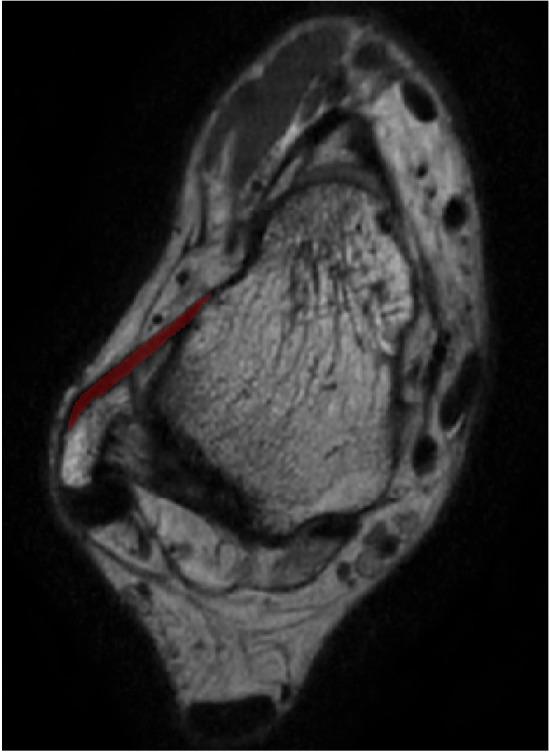

The anterior talofibular ligament (ATFL) is the most vulnerable ligament in ankle sprains. Most patients recover after this injury with conservative treatment, while 20%-40% progress to chronic ankle instability that requires surgical stabilization. Conventional MRI does not provide a comprehensive image of the ATFL. We aimed to evaluate the feasibility of using 3D MRI to facilitate the understanding of ATFL injuries and the operative planning.

METHODS

A total of 21 healthy asymptomatic volunteers with 30 normally functioning ankles and 13 patients with 18 sprained ankles were studied. MRI scans were divided into two groups: Group 1 (normal ankle) and Group 2 (injured ankle). The data of all 48 cases were exported to Mimics and reconstructed into 3D models. The image quality of all 3D models was evaluated using a 5-point subjective scoring system. The length, width, and thickness of the ATFL were measured in the 3D model in Mimics and compared to the 3D MPR image data.

The image quality score was 4.57 ± 0.32. There was no statistically significant difference between the 3D model and the 3D MPR image of ATFL measurements in both groups ( > 0.05).

We concluded that 3D MRI can be used to reconstruct a 3D model of the ATFL for accurate measurements of the ATFL anatomical structure, which holds potential to improve preoperative planning and intraoperative navigation for young sports medicine doctor, facilitate diagnosis of ATFL injuries and make the decision about the operative method.